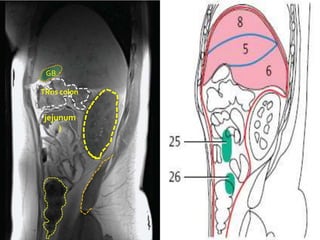

GB

TRns colon

jejunum